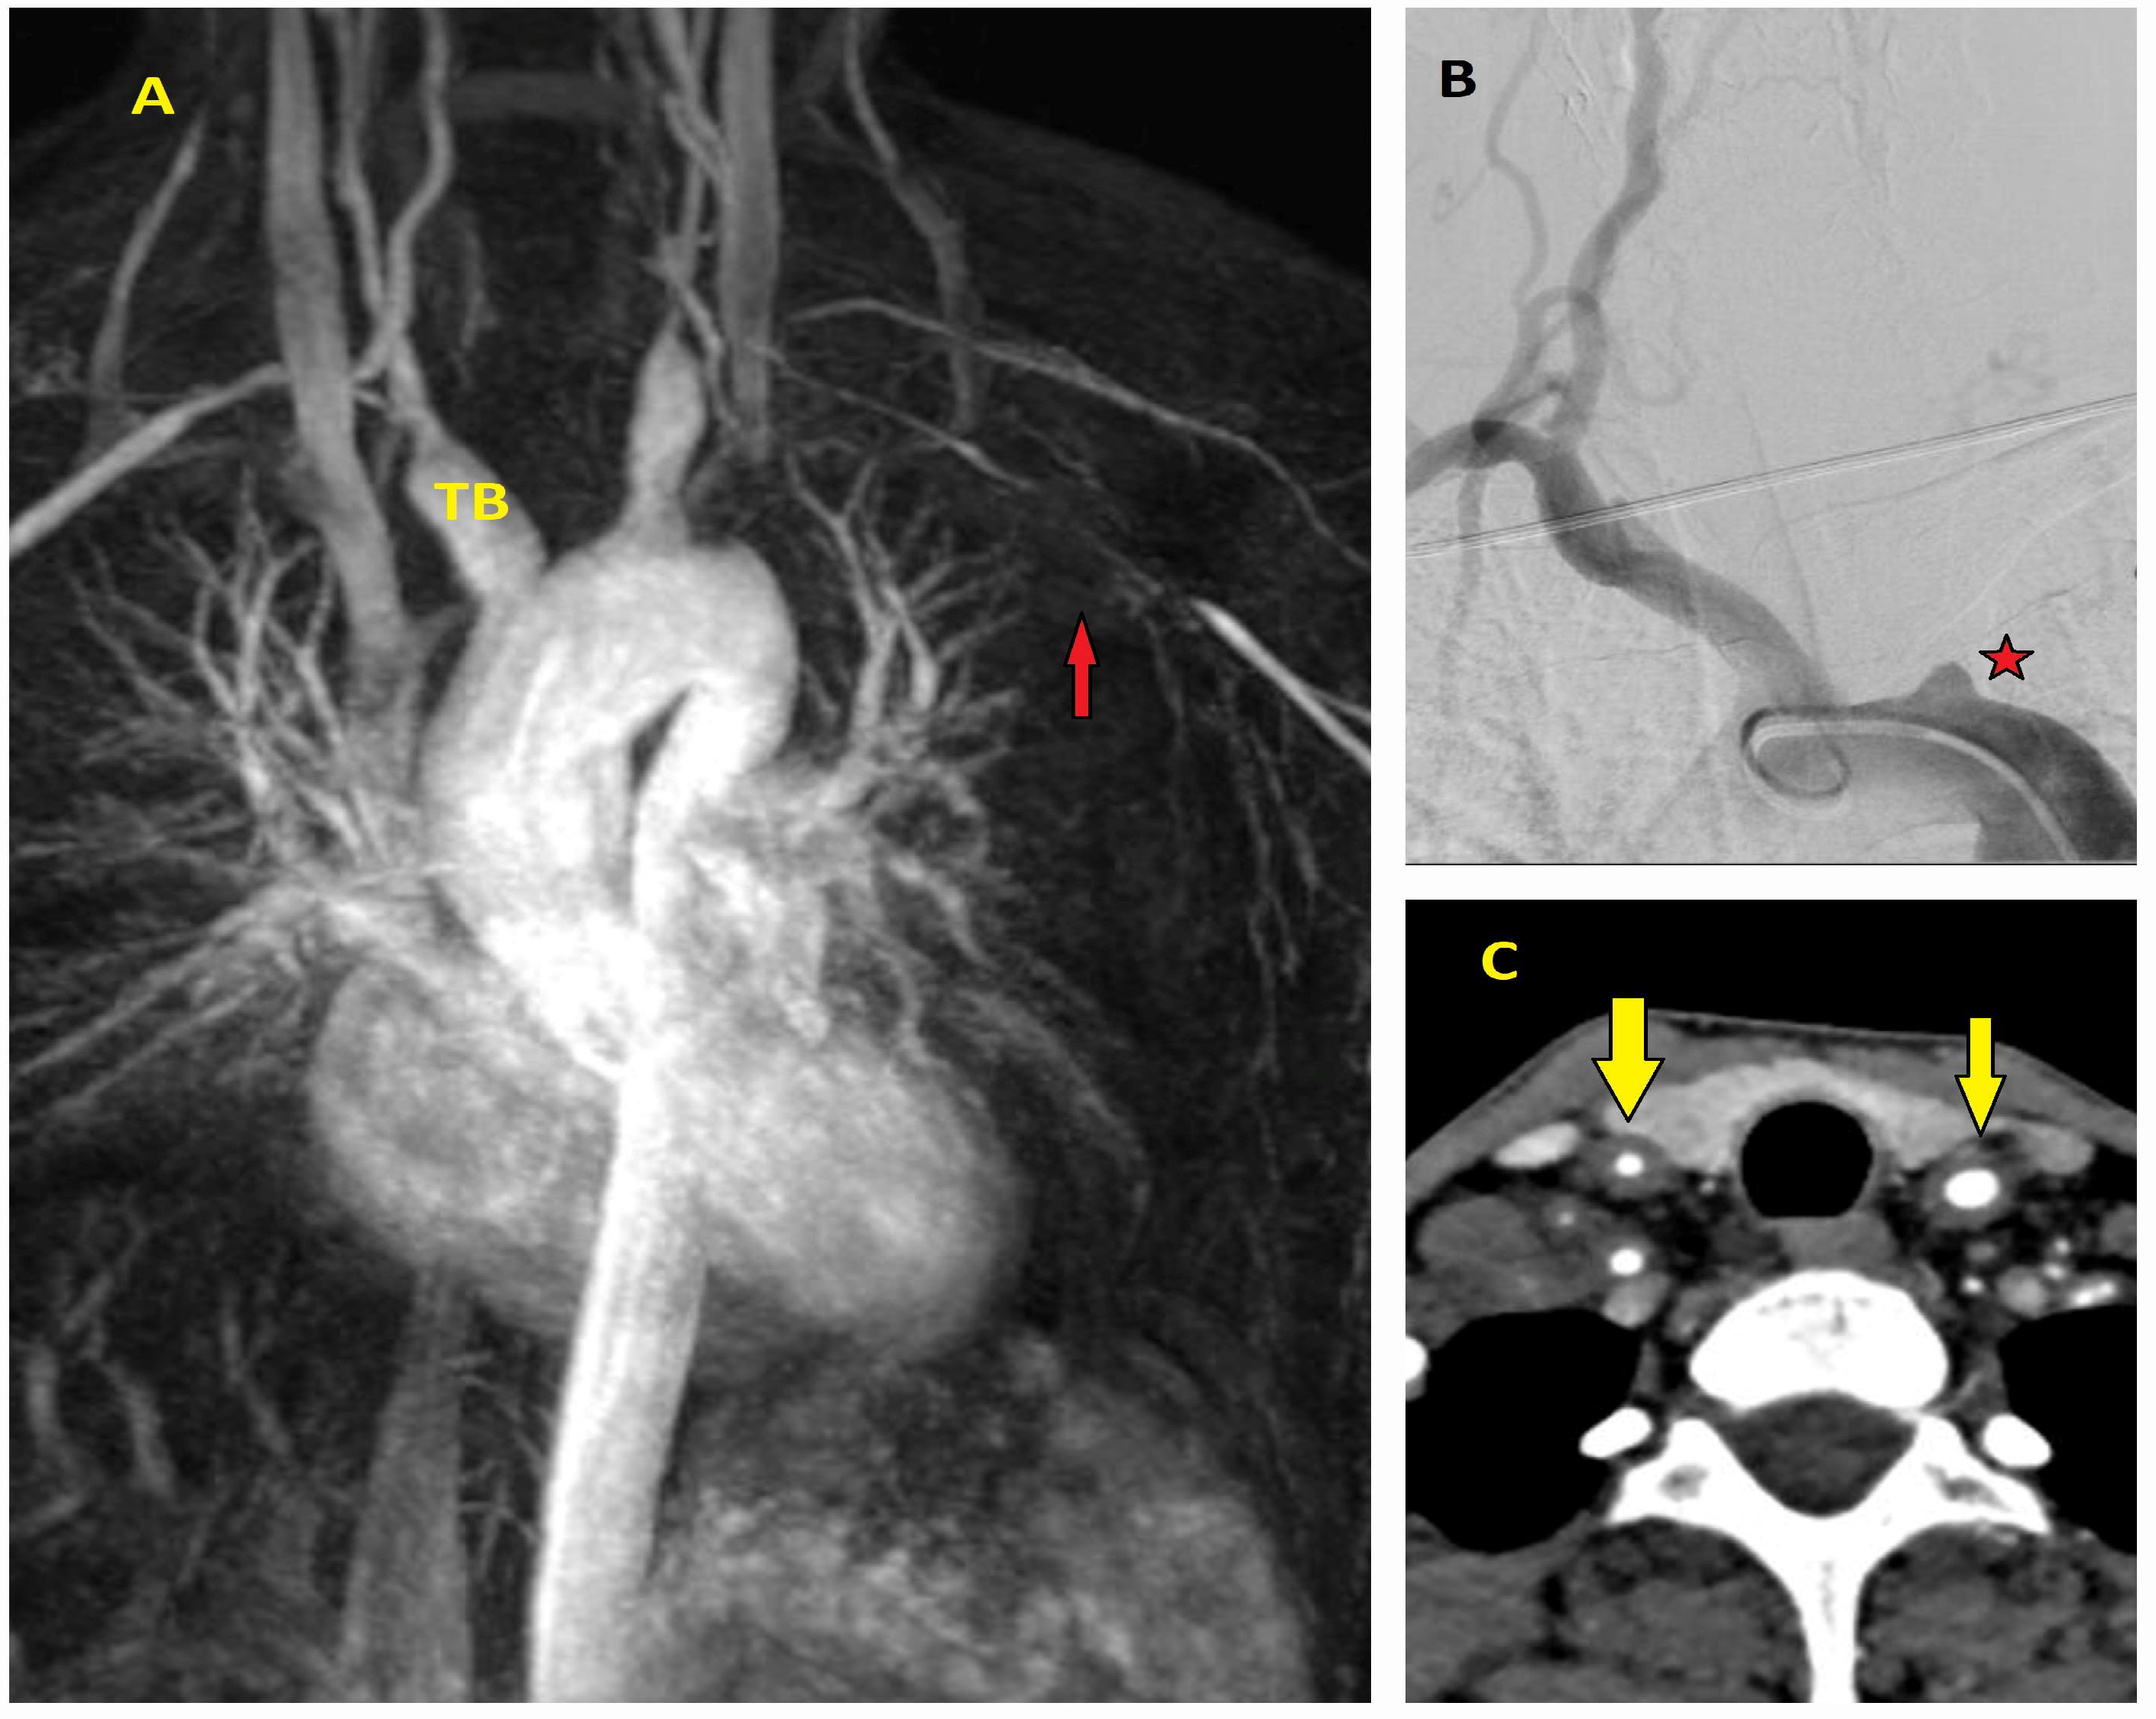

5.2.4. Magnetic Resonance Imaging (MRI)

5.2.3. Computed Tomography